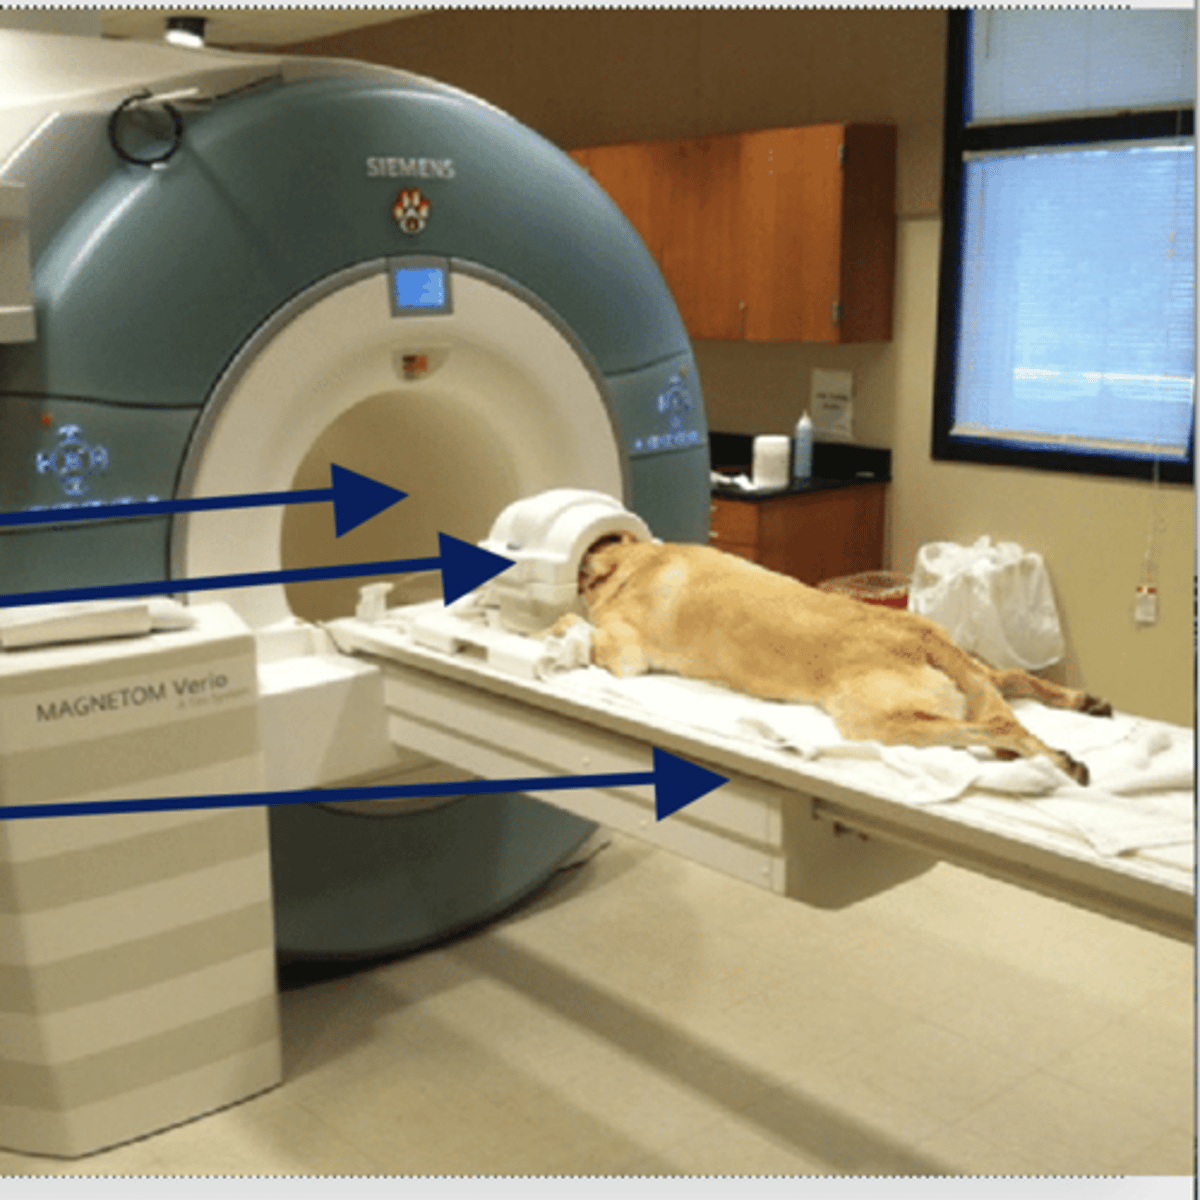

top- bore

middle- RF coil

bottom- couch/table

what are the parts of the MRI machine from top to bottom?

MRI, takes a long time and LOUD

does CT or MRI REQUIRE general anesthesia? why?

does strength matter in MRI?

better

the higher the main magnet field strength usually the _______ the images

tesla (T)

what is the unit of magnetic field strength?